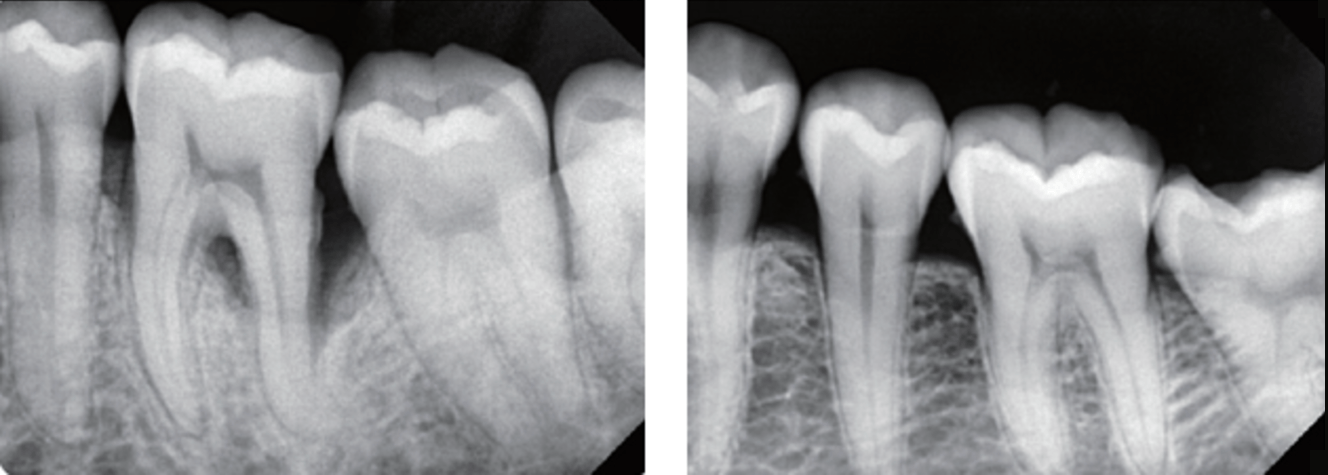

It provides consistently higher resolution and clearer images for accurate diagnosis and treatment planning.

Accurate diagnostic images will be captured with the world’s smallest pixel size.

At 14.8 μm, the EzSensor Soft has a theoretical resolution of 33.7lp/mm.